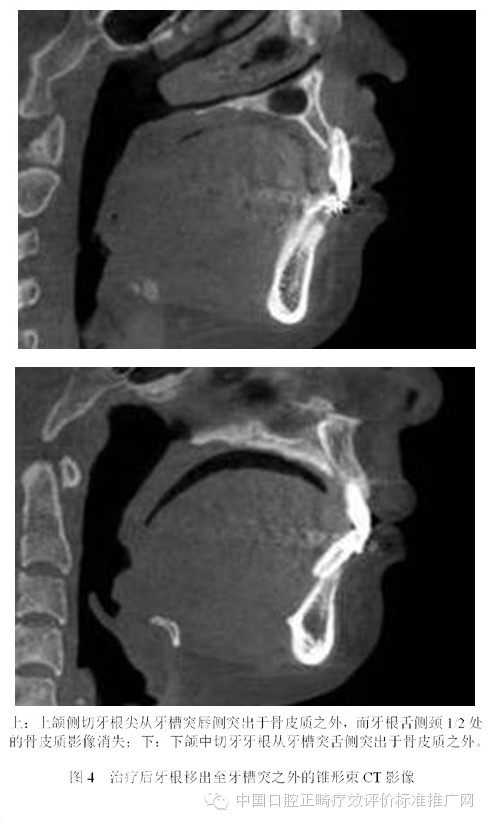

為了避免支抗的丟失,正畸醫(yī)師終于發(fā)現(xiàn)了最強的支抗裝置---金屬種植釘支抗。在用支抗磨牙拉前突的切牙時,切牙牙根在接觸腭側骨皮質后移動的阻力會非常大,于是支抗磨牙會前移而最終關閉間隙;但當改用種植釘支抗拉前牙時,由于種植釘是絕對支抗,在矯治力作用下幾乎不動[6],因此當切牙牙根與腭側骨皮質接觸后,種植釘仍然不會作任何讓步,那么進一步對抗的結果會怎么樣?理想的結果是腭側骨皮質的牙根一側發(fā)生骨吸收,而舌側骨板發(fā)生骨沉積,牙齒帶著牙槽骨一起向腭側移動。問題是骨吸收與骨沉積的數(shù)量相等嗎?速度一致嗎?為了回答這個問題,筆者[7]10年前作過一個上頜切牙內收對其前后方牙槽骨改建的探索性研究。該研究選擇55例平均年齡為13.3歲的青少年錯合患者為研究對象,采用拔除上下頜第一前磨牙進行矯治,平均保持時間為3年。通過測量上切牙阻力中心前方及后方牙槽骨在治療前、治療后及保持后的骨量變化,以及牙槽突總厚度在上述3個時間點的變化,結果發(fā)現(xiàn):上切牙阻力中心在治療后向腭側平均移動了1.8mm (P<0.001);與阻力中心水平的唇側牙槽骨厚度增加了0.2mm (P<0.01),腭側牙槽骨厚度減小了0.8mm (P<0.001);隨訪期上切牙阻力中心向唇向復發(fā)了0.8mm (P<0.01),與阻力中心水平的唇側牙槽骨厚度相應減小了0.2mm (P<0.05),但腭側牙槽骨厚度卻并沒有明顯的增加;與上切牙阻力中心水平的牙槽突總厚度基本保持在治療后的水平。由此可見,在牙齒移動的過程中,牙槽骨的生物學改建是以骨吸收為主,骨增生十分有限,即使是保持3年以后,骨增生的量也未達到其吸收的量。雖然這只是個初淺的臨床研究,尚有待基礎研究去證實,但它卻部分解釋了正畸臨床上在對骨性錯合患者進行牙代償性矯治時,會出現(xiàn)牙槽骨吸收、裂隙、穿孔,牙齦萎縮或部分根尖移出牙槽骨的現(xiàn)象[8-13]。圖3為1例成人患者在用牙代償性治療方法減少重度深覆蓋深覆合時出現(xiàn)切牙根尖從舌側移出牙槽骨的X線影像;圖4為1例采用種植釘支抗大量內收上下頜前牙的患者,治療后牙根移出至牙槽突之外的錐形束CT影像。

目前尚不清楚正畸過程中出現(xiàn)骨開窗或骨開裂的危害,對CT影像上牙根突出于骨皮質之外多少會出現(xiàn)有臨床意義的骨開窗或骨開裂也不得而知,更不清楚由正畸牙移動造成的骨開窗或骨開裂能不能自行修復。雖然這些問題尚無明確的答案,但是從牙周健康的角度考慮,任何醫(yī)師都沒有理由相信牙根在牙槽骨之外會比在它本來應該位于的牙槽突之內更加健康。由此可見,正畸支抗并非越強越好。70多年以前,正畸學先驅Tweed醫(yī)師考慮到牙弓唇頰側的邊界,提出了拔牙矯治的概念;今天,當種植釘支抗風靡全球之際,當正畸醫(yī)師有能力將前牙無限內收之時,難道不該問一句:“牙弓的舌側有沒有邊界?”